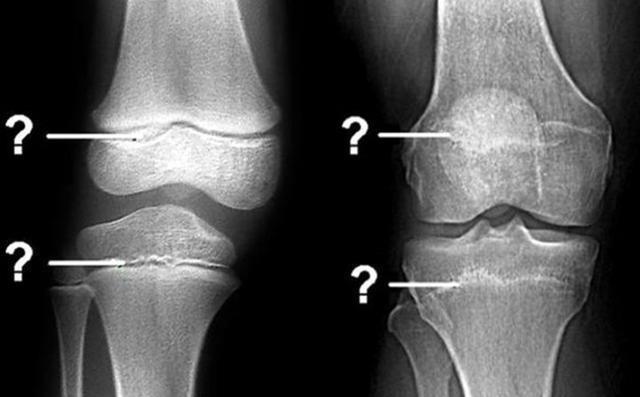

骨骺线闭合是孩子“身高”封锁的信号,要想蹿出高个子,家长要有数

在一些家长看来,判断孩子是否还有发育潜力的关键在于年龄,事实上,这种判断并不准确,

相反,骨骺线才是决定孩子能否长高的关键参数。

▼什么是骨骺线?

骨骺线其实指的是骨骼之间的软骨层,这些软骨层之间会存在一定的空腔,这些空腔的存在就为接下来的身高发育提供了无限的可能。

体内的骨细胞会在空腔中不断增殖再生,同时骨质化,从而让宝宝不断长高。

文章插图

相反,如果孩子的骨骺线出现了闭合,那么说明软骨层的空腔已经闭合,

骨细胞没有“地方”转变为骨质帮助长高

,孩子的身高发育也就告一段落。